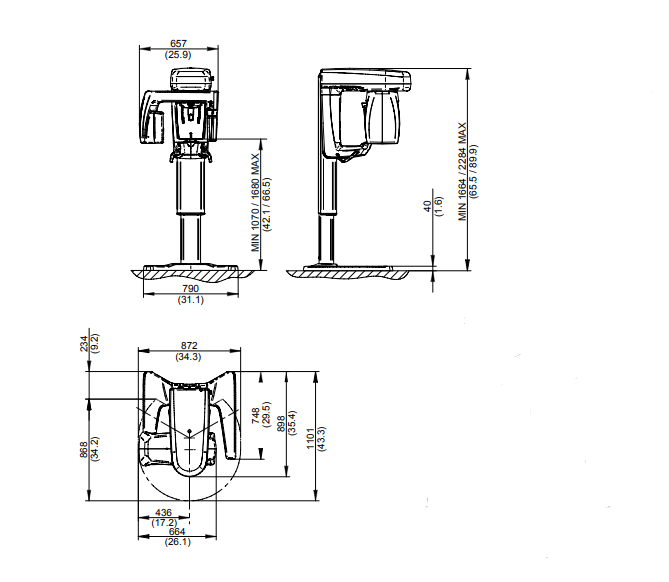

GO 2D/3D имеет один собственный 16-битный датчик, который создает 2D и 3D изображения с тысячами уровней серого. Качество изображения обеспечивается передовыми алгоритмами и протоколами, а также высокотехнологичной последовательностью изображений. Высокочастотный генератор импульсного излучения регулирует экспозицию для получения наилучшего сканирования с минимальной дозой. Кроме того, система коллимации цефалометрического обследования основана на автоматическом перемещении турели, которая поворачивает и опускает датчик, создавая отверстие для рентгеновских лучей, направленных на 2D-датчик на теле радиографическом рычаге. Благодаря пяти контактным точкам поддержка головки 3D-сканирования помогает персоналу правильно и комфортно позиционировать пациента. Точки фронтального и бокового контакта могут быть отрегулированы таким образом, чтобы максимально повысить стабильность пациента во время сканирования и, следовательно, качество полученных данных. Специальный протокол позволяет проводить томографическое сканирование рентгенологических шаблонов, протезов, моделей или оттисков после их установки на специальную подставку.

Превосходный комфорт для быстрого и стабильного позиционирования пациента. Разработанный для обеспечения отличного позиционирования пациента, GO 2D/3D позволяет быстро находить правильное положение для обследования, которое всегда идеально. Само-адаптивные функции GO 2D/3D позволяют проводить точные исследования с использованием высококачественных, диагностически ценных изображений. У оператора есть инструменты для позиционирования пациента и направленного выравнивания для достижения идеальной фокусировки.Комплектация

Созданный, чтобы обеспечивать отличное положение пациента, GO 2D/3D позволяет моментально находить правильное положение для всегда идеального обследования. Самоадаптивные функции GO 2D/3D позволяют проводить точные обследования с качественными, диагностически ценными изображениями. Оператор имеет в распоряжении инструменты для расположения пациента и управляемое выравнивание для достижения идеальной фокусировки.